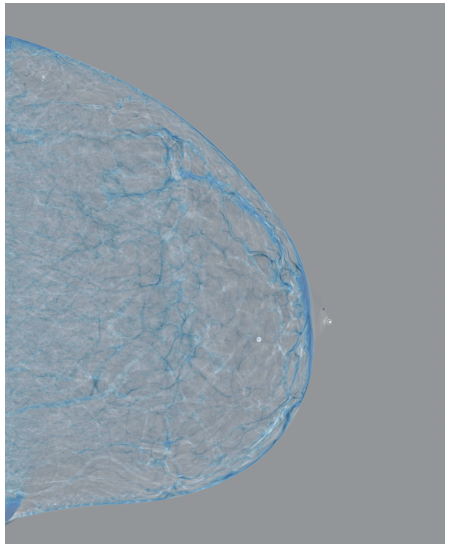

4.3 Pre-processing

The EMBED and CSAW-CC datasets originally consist of images in DICOM format, which are converted into 16-bit grayscale PNG images for consistency and compatibility. Following the pre-processing procedure outlined in (Yala et al.,, 2021), we enhanced image quality and removed background artifacts—such as textual annotations commonly present in mammography images—by applying a contour detection procedure. All contours in the image are detected, and only the largest contour, corresponding to the breast tissue, is retained. This contour is then used to create a mask that isolates the breast region from the background. The isolated breast image is resized to a size of 1664×20481664\times 2048 pixels while preserving the aspect ratio. Finally, the resized image is normalized and converted to a 16-bit format.

Following (Wang et al.,, 2024), we included only patients with at least five years of follow-up data for risk prediction. The datasets are randomly split at the patient level into training, validation, and test sets in a 5:2:3 ratio. Table1 presents the distribution of the Time-to-Cancer label and the dataset split for both the EMBED and CSAW-CC datasets.